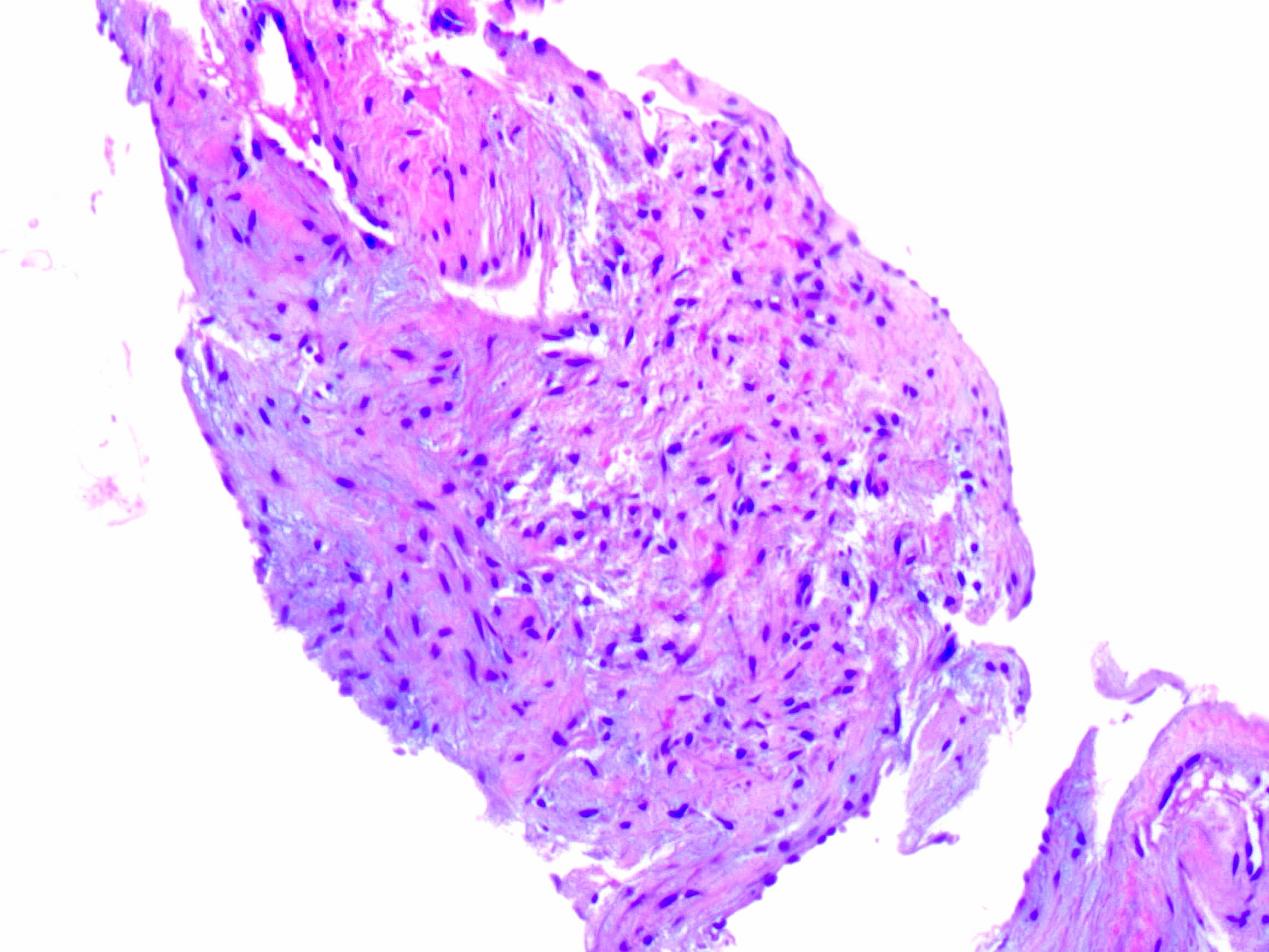

| 图 2 组织病理学检查 |